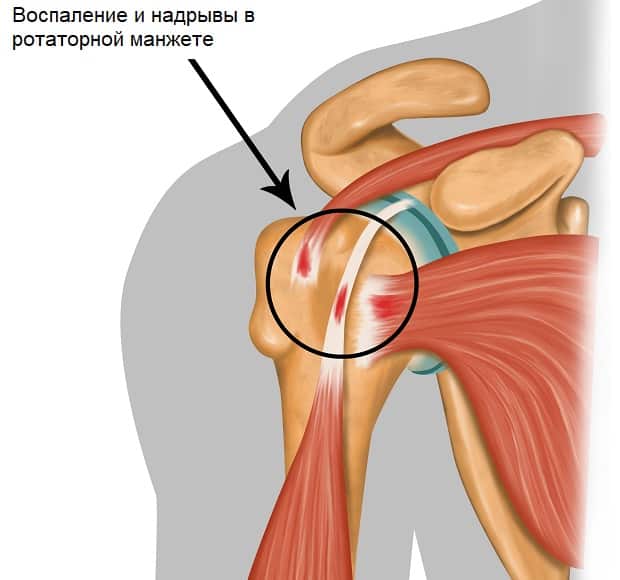

Фотографии мышц ротаторной манжеты плеча